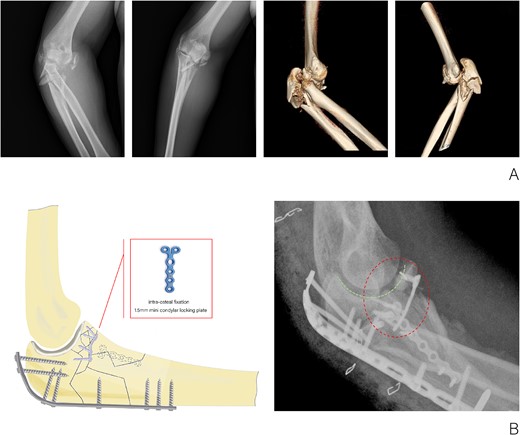

The patient, a 36-year-old male, sustained a direct trauma to the elbow joint resulting from a forceful fall and impact with the ground. The diagnosis revealed a right Monteggia fracture, accompanied by posterior elbow dislocation and ulnar nerve injury. Examination revealed no external wounds on the elbow joint. Furthermore, preoperative assessment confirmed that the blood supply, ulnar nerve, radial nerve, and central nerves of the affected limb remained intact. A plaster was used to fix the elbow in the flexor position temporarily. Three-dimensional CT reconstruction clearly indicated an O’Discoll III fracture of the coronoid process, which was fragmented into three discrete bone fragments. Additionally, there was evidence of a comminuted fracture of the olecranon as well as a fracture of the radial head (Fig. 1A).

(A) X-ray and CT three-dimensional reconstruction examination of elbow fracture. (B) Diagram of intra-osteal fixation of comminuted coronoid process fracture with mini plate and postoperative X-ray examination of the elbow.